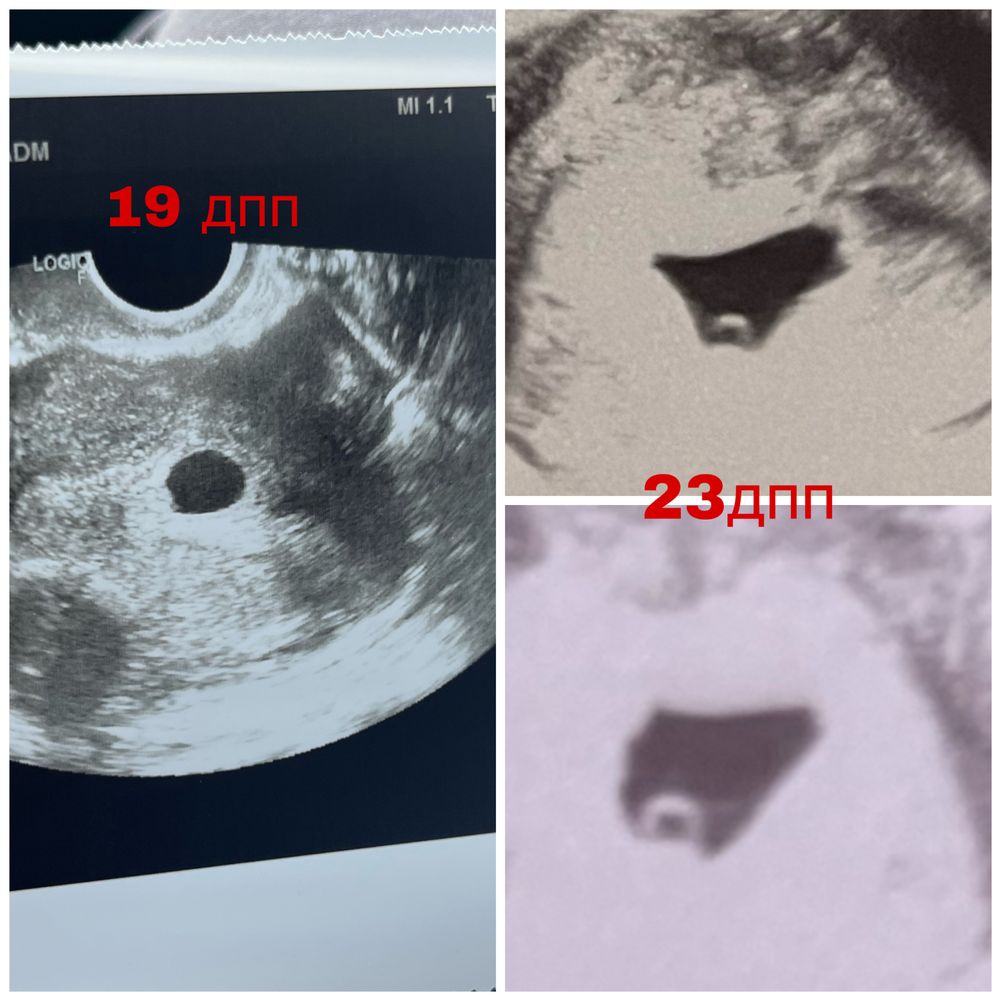

23 дпп нет эмбриона

узи на 19 дпп: пя 11 мм, жм 1,5 ктр-

узи на 23 дпп: пя 16мм, жм 4,9 мм ктр-

Даже по фото узи есть хорошая динамика . Нужно сделать узи у другого специалиста. Может срок ещё маленький и надо подрасти крошке!